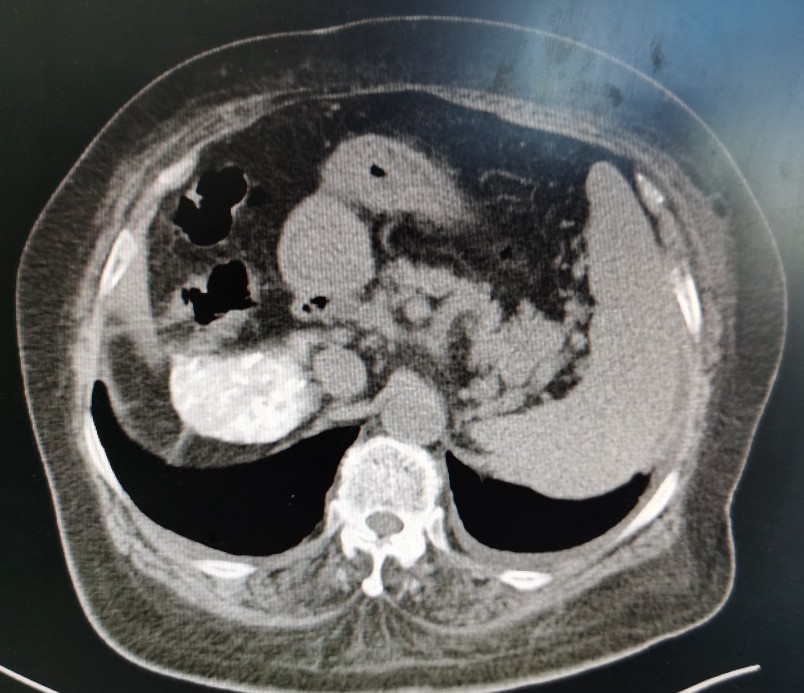

栓塞后复查的CT

栓塞后CT

肿瘤栓塞良好